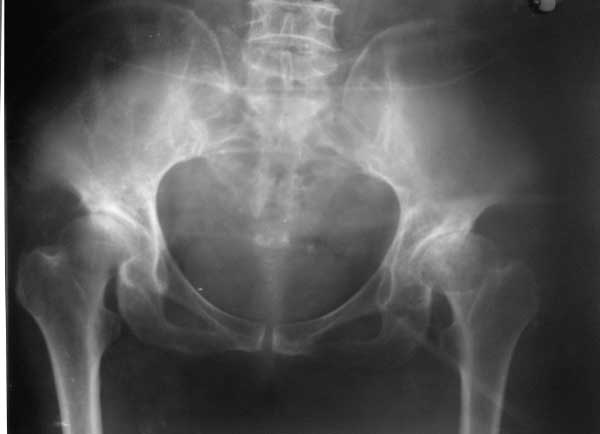

以下是引用yxfjnchina在2005-4-16 19:51:36的发言:[br]双侧髋臼稍浅平,髋臼外上缘可见骨质增生.左股骨头内密度不均,可见小囊状低密度影及不均匀硬化.小梁紊乱.考虑双侧髋臼发育不良并退行性骨关节病.左股骨头缺血性坏死待排

以下是引用dgma在2005-7-1 21:34:00的发言:[br][br]双侧髋臼发育不良。[br]退行性骨关节病。[br]左股骨头缺血性坏死?[br]建议:左股骨头mr扫描。